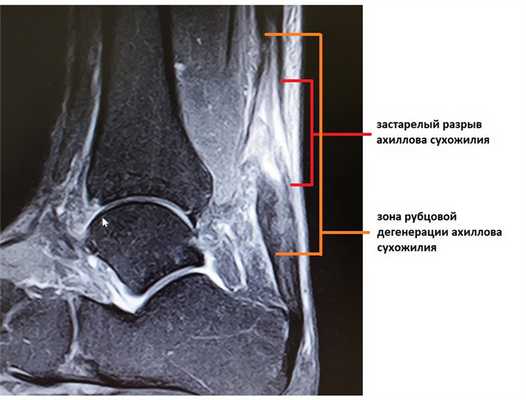

Помимо клинической картины важно и инструментальное обследование. Для планирования оперативного вмешательство наиболее актуально использование МРТ. Благодаря МРТ можно не только получить инструментальное подтверждение диагноза, но также оценить размеры дефекта, степень дегенеративных изменений свободного конца сухожилия, запланировать уровень резекции пяточной кости и предположительную удалённость зоны удлиняющей сухожилие пластики.

В такой ситуации дефект ахиллова сухожилия может быть даже больше чем при обычном застарелом разрыве, так как дистальный конец сухожилия дегенерирует и кроме того производится резекция небольшого участка пяточной кости, для того чтобы подготовить «посадочную площадку» для сухожилия.

При МРТ исследовании определяется обширная зона дегенерации сухожилия, значительно превышающая размер дефекта.